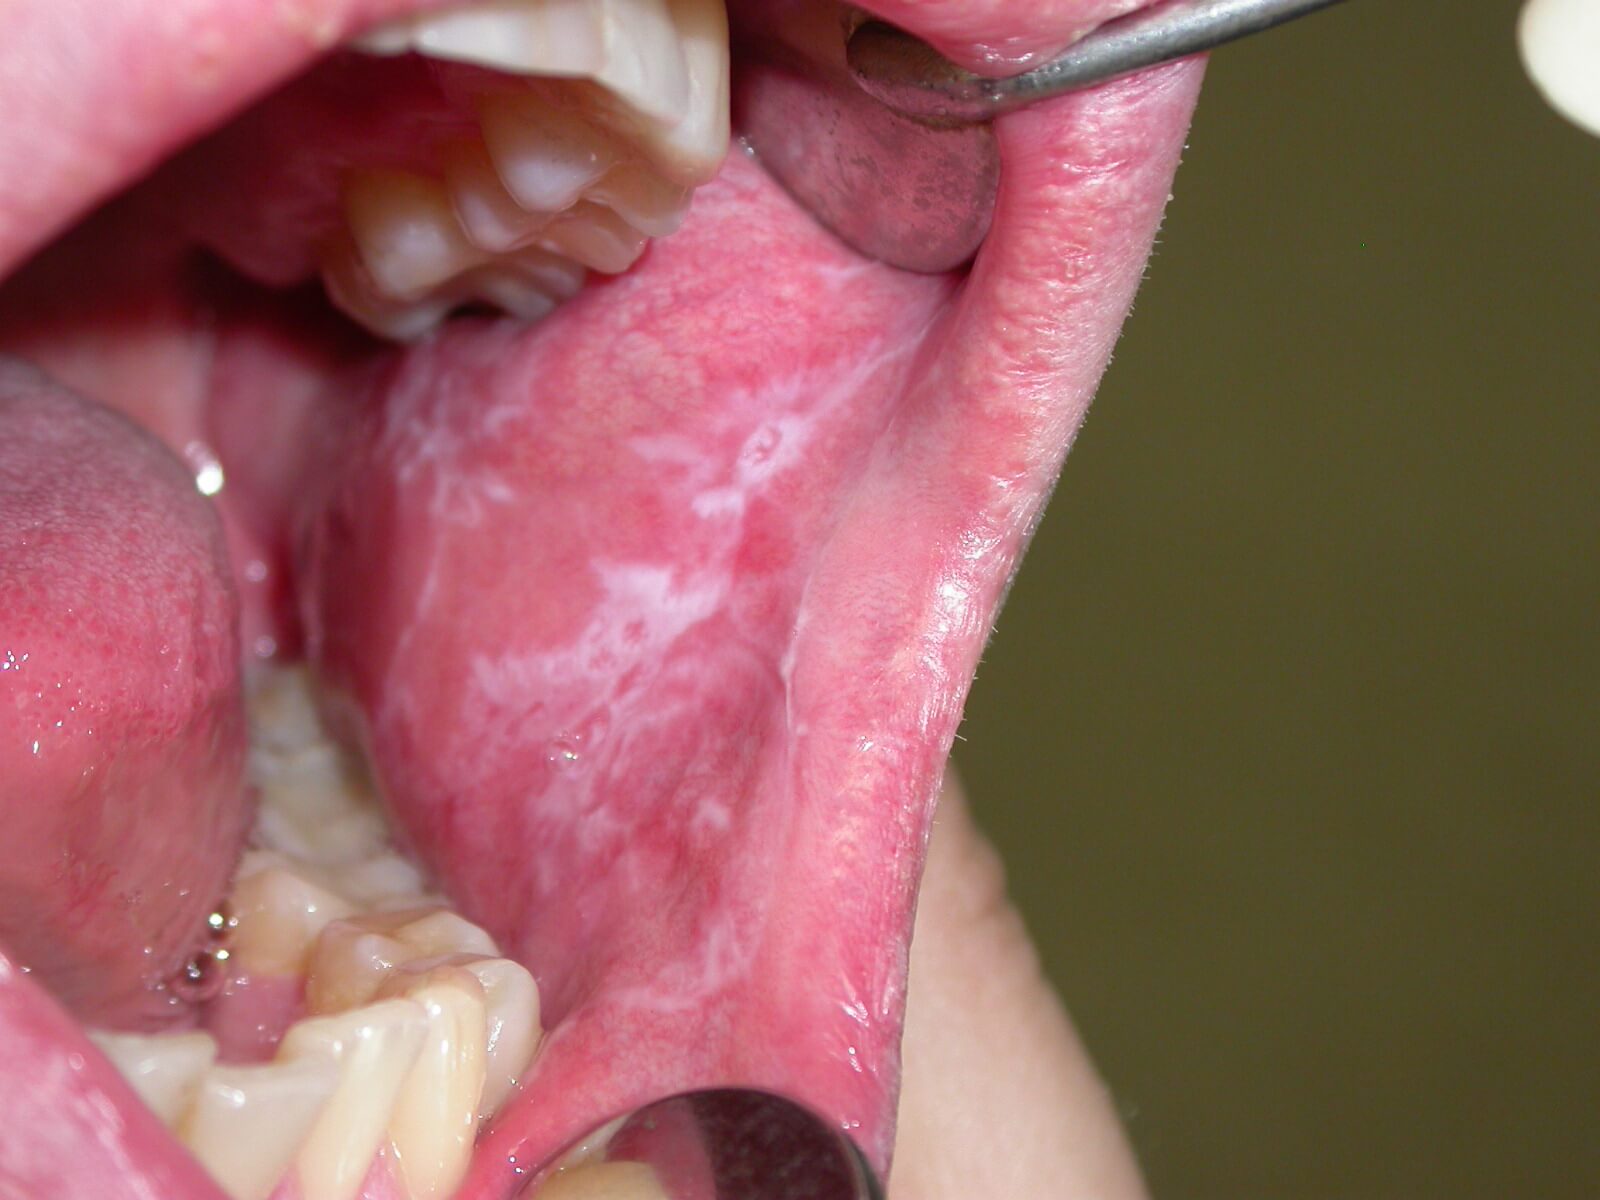

Якщо говорити про показання до застосування препарату, то вони представлені незначними інфекціями ротової порожнини.

Зокрема, йдеться про кандидоз, біль у горлі, гінгівіт, афтозні виразки, неприємний запах з рота.